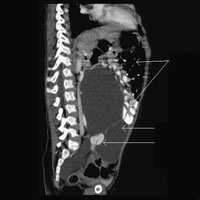

患儿,女,2岁,因发现腹部囊性肿物6天入院。各项实验室检验均未见异常。CT平扫及增强后显示腹膜后巨大囊性占位性病变,密度均匀,其间可见分隔;肠管及膀胱受压移位,左肾未见异常,右肾区未见肾影,于盆腔左侧、髂动静脉的前方可见一强化明显的小肾(图1、2)。CT及超声诊断为腹膜后淋巴管瘤、右肾发育不良、异位。术前诊断为腹膜后淋巴管瘤合并右肾发育畸形。病理诊断:右侧多囊性肾发育不良,残存小肾皮髓结构不清,输尿管远端闭锁(图3)。